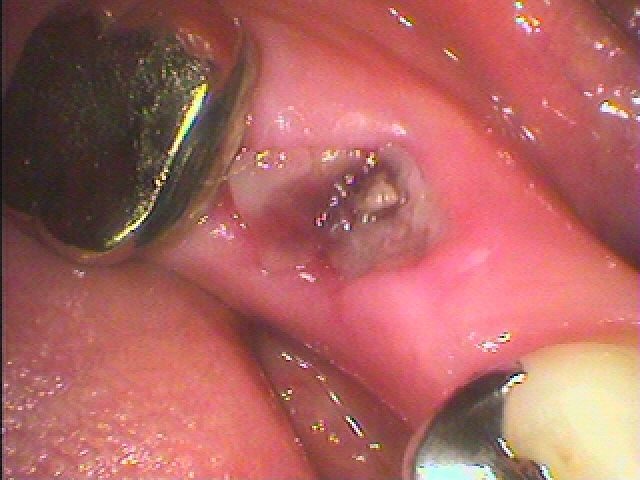

左下の奥歯のインプラント埋入|お知らせ |広島市安佐南区の歯科医院 左下の奥歯のインプラント埋入 トップ お知らせ・ブログ お知らせ 左下の奥歯のインプラント埋入 左下の奥歯のインプラント埋入 左下の6番ヘミセクション このクラウンが揺れてきました 骨吸収が認められます 割れているため抜歯となりました 抜歯しました 埋入していきました 補填材を入れ縫合して終了です このように埋入しています Web診療予約 初めての方へ 選ばれ続ける理由 院内設備について 歯が痛いしみる一般歯科 歯がぐらぐらする歯周病 健康な歯を保ちたい予防歯科 子供の虫歯予防をしたい小児歯科 銀歯をセラミックに審美歯科 白い歯を目指しませんか?ホワイトニング 矯正専門医がいるので安心矯正歯科 抜けた歯を補いたいインプラント・入れ歯 医院案内 スタッフ紹介 メリィハウス歯科クリニックオフィシャルホームページ ラベンダー歯科クリニックオフィシャルホームページ お知らせ・ブログ ホーム 診療科目 一般歯科 歯周病治療 予防治療 小児歯科 審美治療 ホワイトニング 矯正歯科 入れ歯・インプラント マウスピース矯正 初めての方へ 院長・スタッフ 設備紹介 医院案内・アクセス メニューを閉じる